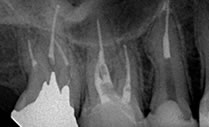

2008年6月

オブチュレーションシステムを用いて根菅充填:根尖までオブチュレーションガッタが充填されているのがわかります。根尖孔から少しオーバーしているのがポイントです。

側枝

近心に側枝があります 。オブチュレーションなら側枝まできれいに根菅充填できます。

RCF

根尖まできれいに充填されています。